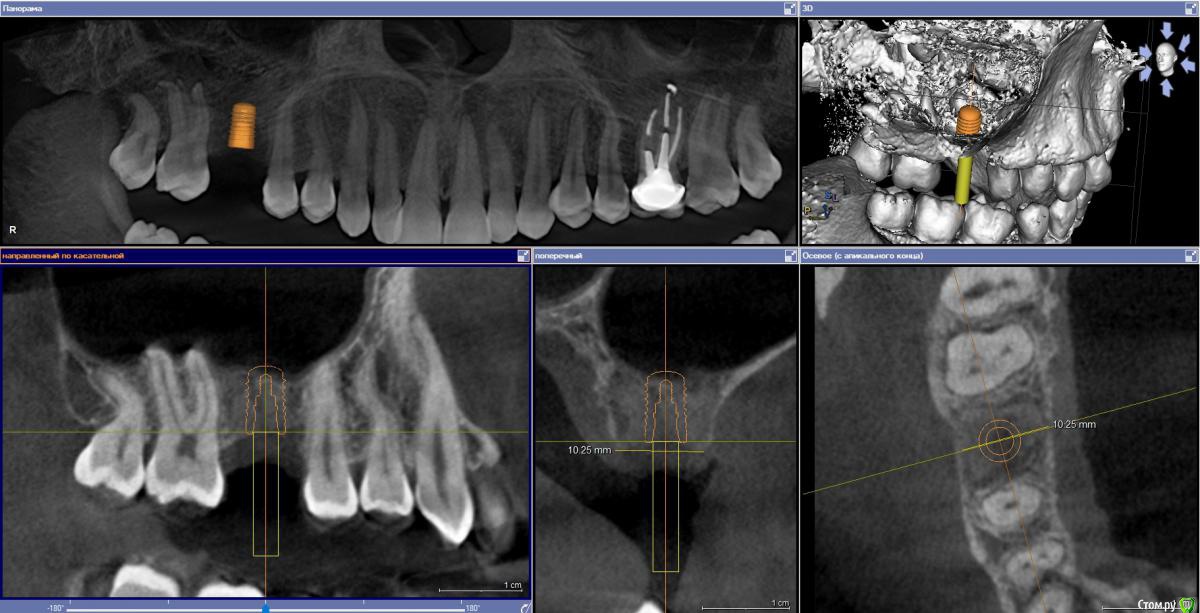

Ponchik Опубликовано 27 сентября, 2018 Поделиться Опубликовано 27 сентября, 2018 (изменено) Планируется Штрауманн Бон Левел 4.8-8 в области 1.6. Думаю дойти до 6,5 и далее стукнуть пару раз. Вкрутить и забыть. На 3-4 месяца. Это же не лень? Правда? Да и дно там не ровное, отслойка может запороться... Изменено 27 сентября, 2018 пользователем Ponchik Ссылка на комментарий

Nazim_NV86 Опубликовано 27 сентября, 2018 Поделиться Опубликовано 27 сентября, 2018 Измерение высоты не вижуПоэтому не понятно 6.5 до куды будет Ссылка на комментарий

Ponchik Опубликовано 27 сентября, 2018 Автор Поделиться Опубликовано 27 сентября, 2018 Измерение высоты не вижу Дык имплантат 8 мм. А как на счет коротышек штраумановских? Мне ортопед одиночки по 6 мм не советует ставить. Вот ведь злобная хирургическая братия! Вам лишь бы стукнуть! ТОЧНО!!! Всё остальное предлог!!! 1 Ссылка на комментарий